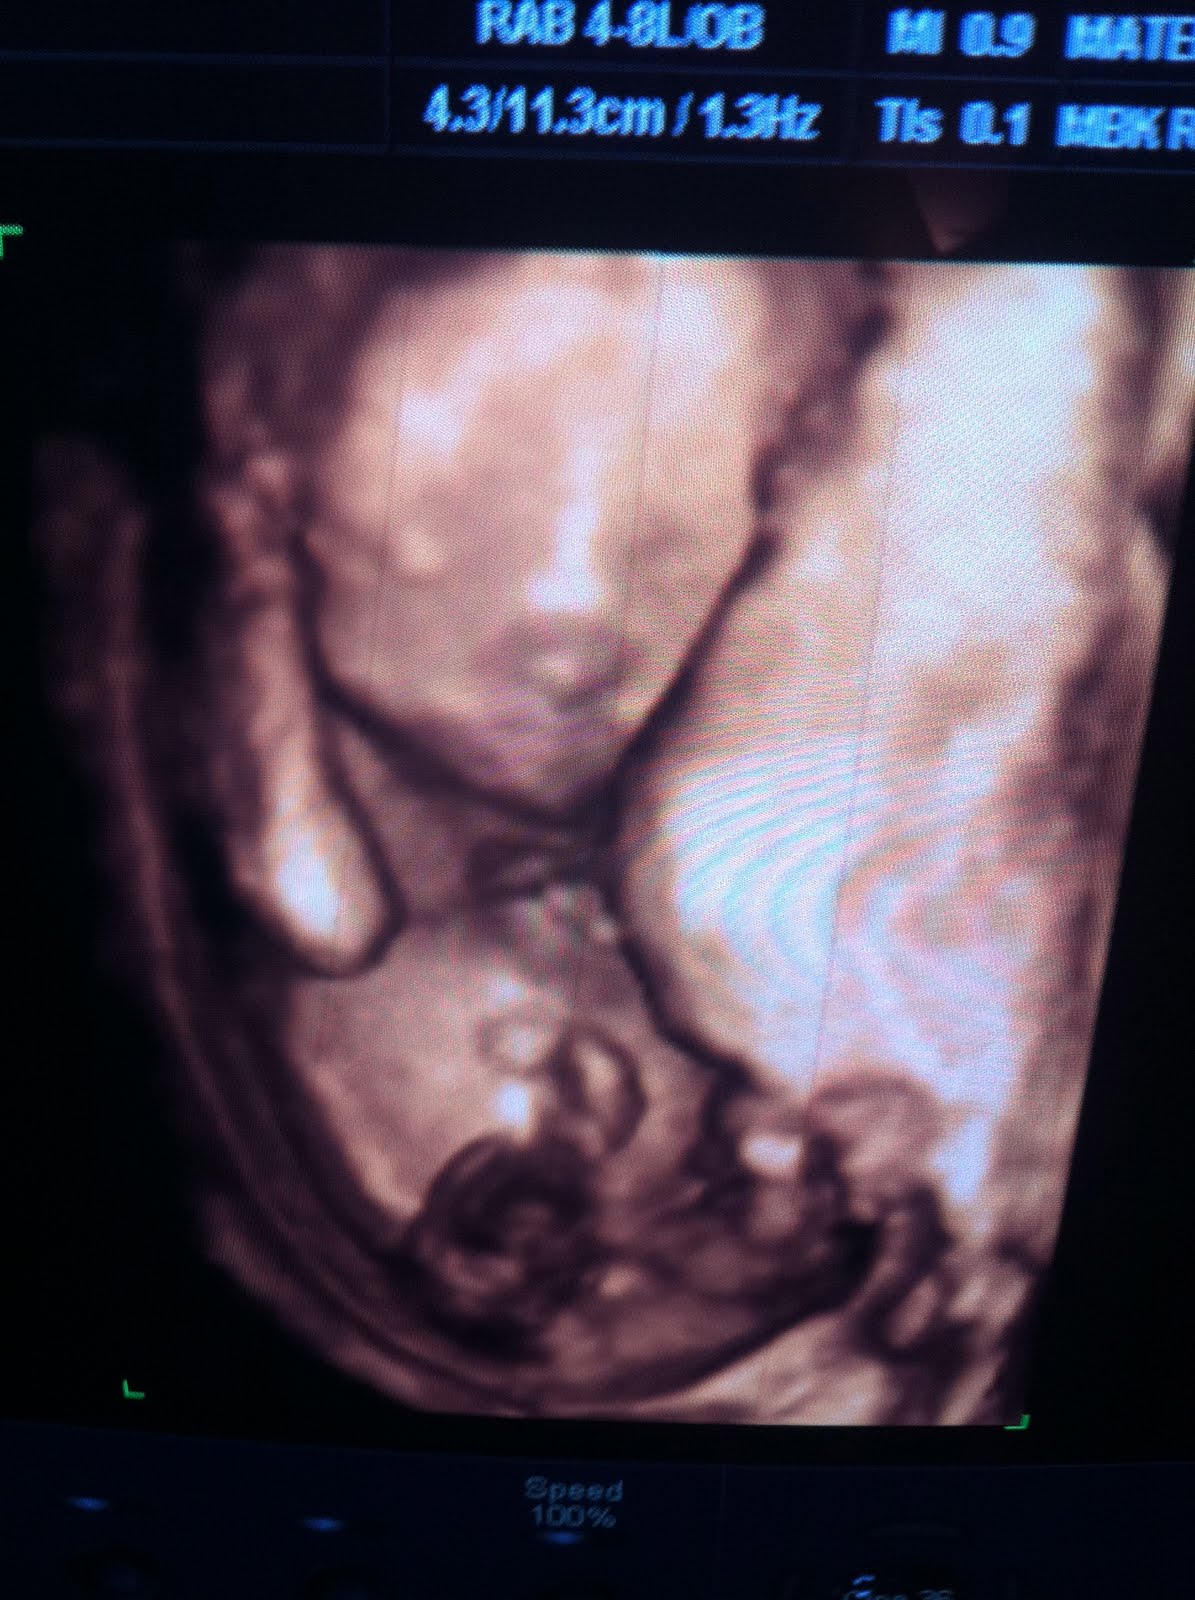

We had an incredible ultrasound today! I have to say our doctor's office has become like family to us. They have been with us through the good, the bad, and the ugly & still greet us with a smile when we walk through the door. You know you call WAY too much when everyone in the office knows you by name! I have been good though...I haven't called to ask a question in THREE week!! That is good for me:)

First and foremost, Copelyn is still a GIRL! We took the chance and told everyone we were having a girl after 16 weeks knowing there would be a slight chance they could be wrong. We were relieved when Copelyn gave us a clear shot and we could tell for sure she was a girl! Good thing because her room is already pink, she already has monogrammed clothes, and her bedding is pink! We would have been in trouble!

Copelyn was perfect! She had ten fingers, ten toes, and the cutest little nose. She also had long legs & quite the little butt! She wouldn't be my child though if she didn't have some kind of butt! Sorry Copelyn it just runs in our family! All of her organs looked perfect! It amazes me every time I see her! I am so thankful God intricately designed her to make her unique in his image. I think he did a great job!

We got a lot of images today but I didn't have time to scan them so here is some taken with my phone! I will post more later!